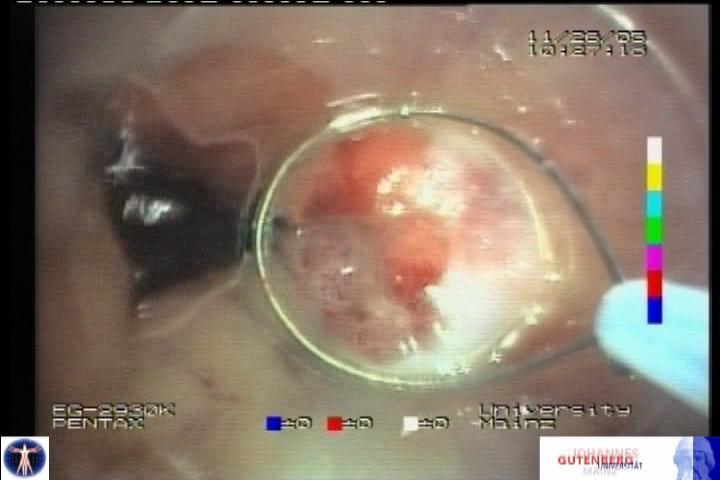

El esófago de Barrett con displasia severa o carcinoma intramucoso es suceptible de un tratamiento endoscópico con intención curativa. Sin duda, la mejor técnica es la disección endoscópica submucosa (ESD), pero es compleja, con una tasa de complicaciones no desdeñable y está muy poco extendida en Occidente. La mucosectomìa endoscópica es una alternativa bastante mas sencilla, con % de complicaciones menor, que si ha tenido aceptación en los paises occidentales. Los dos métodos mas difundidas son el sistema de bandas Duette (Cook) y el de Caps sin ligadura (Olympus). El primero es algo mas sencillo ya que es muy similar a la ligadura de varices con bandas. Se exponen dos ejemplos de las técnicas descritas del DAVE Project: